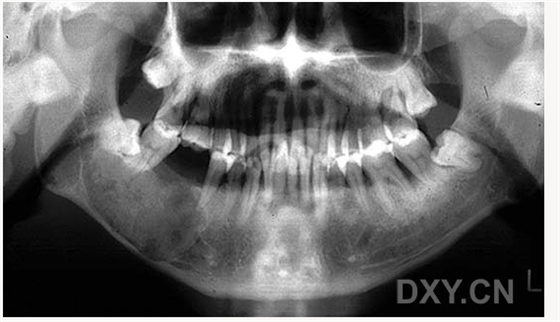

球狀上頜囊腫

含牙囊腫

球狀上頜囊腫    含牙囊腫